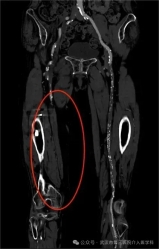

经过检查,结果令人心惊:下肢动脉硬化闭塞症,她的左腿主干血管几乎被堵死了!脚趾发黑正是肢体坏疽的征兆,如不及时处理,等待她的很可能就是截肢。

支架前造影图

面对李奶奶的危急情况,截肢似乎是无奈的选择。但我们的医疗团队决定为她打一场“保腿之战”!我们为她实施了 “下肢动脉造影+球囊扩张成形术”。